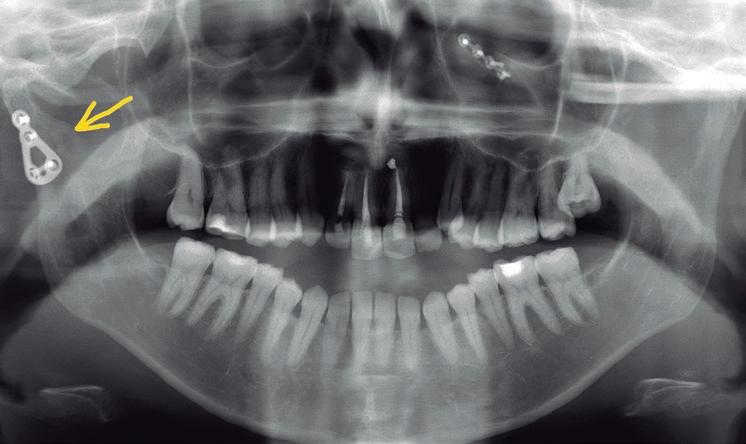

SFIG. 1, a-e. Fractura subcondílea derecha tipo V de Spiessl en una paciente joven tras un accidente doméstico. a) OPG preoperatoria donde se aprecia la línea de fractura subcondilar derecha con desplazamiento fragmentario (flecha roja) y el movimiento de dislocación ántero-medial que ha realizado el fragmento condilar (flecha amarilla); la paciente había sufrido una fractura orbitaria hacía unos años, observándose una miniplaca de titanio colocada en el reborde infraorbitario izquierdo. b) Corte axial y densidad hueso de la TC con el fragmento condilar dislocado adelante hacia medial muy cercano a la apófisis pterigoides (flecha verde) aunque con aparente contacto entre fragmentos (flecha roja). c) Corte coronal de la TC con el desplazamiento entre fragmentos (flecha roja) y la dislocación hacia medial (flecha amarilla) fuera de la fosa glenoidea (puntos verdes). d) Vista anterior de la reconstrucción 3D con sustracción de estructuras de la TC en la misma fractura. e) Vista póstero-lateral de la misma reconstrucción; estas imágenes son muy útiles durante la cirugía para apreciar los movimientos en los tres planos del espacio que realizó el fragmento condilar, aunque solamente informa de las estructuras óseas y no de los tejidos blandos.